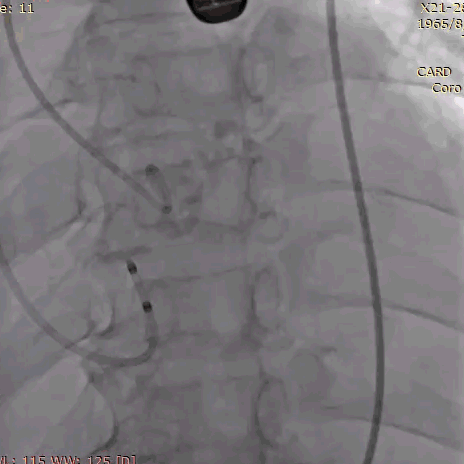

手术影像记录:

植入前冠脉造影

主动脉根部造影

直头导丝跨瓣

20mm球囊预扩

冠脉保护支架植入

AV23瓣膜释放到工作位

瓣膜完全释放

冠脉支架释放

植入后造影